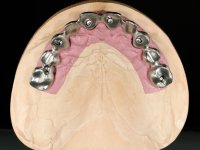

Paciente do sexo masculino, com 64 anos de idade e não fumador. Apresentava uma prótese combinada superior composta por uma ponte metalo-cerâmica fixa de 6 elementos (1.3,1.2,1.1,2.1,2.2, e 2.3) e uma prótese esquelética superior também com 6 elementos. No maxilar inferior apresentava duas pontes metalo-cerâmicas, uma de 3 elementos no 4º quadrante e outra de 2 elementos no 3º quadrante. A adaptação das pontes estava comprometida e esteticamente não satisfaziam o paciente. A higiene oral não era satisfatória.

Realizada uma TAC, foi planificada a colocação de 6 implantes no maxilar superior. Foi decidida a colocação de dois implantes na zona dos incisivos centrais, dois implantes na zona dos caninos e dois na zona dos segundos pré-molares. A ausência de estrutura óssea na zona distal do primeiro quadrante implicava a realização de uma regeneração óssea no seio maxilar direito. A cirurgia foi realizada e após a colocação dos implantes foi feita a impressão para confeção de uma prótese provisória metalo-acrílica aparafusada para colocação em carga imediata no dia seguinte. O implante colocado na zona do seio maxilar direito não foi colocado em carga. Passados 6 meses foi realizada a impressão aos 6 implantes com técnica de moldeira aberta e foram confecionados os modelos de trabalho. Numa consulta seguinte foram montados os modelos de trabalho em articulador semi-ajustável utilizando o arco facial e a relação inter-maxilar obtida com a prótese provisória. Foi feita uma muralha de silicone sobre a ponte provisória com o objetivo de orientar o trabalho laboratorial. Realizada a infra estrutura metálica aparafusada esta foi provada em boca e finalmente após colocação de cerâmica o trabalho foi colocado definitivamente. Como passaram vários meses após a realização da primeira TAC foi feita uma segunda para planificar a colocação de implantes no 4º quadrante. Colocaram-se 3 implantes na mesma sessão em que foi feita a extração dos pilares da ponte. Estes implantes foram posteriormente reabilitados com uma ponte metalo-cerâmica aparafusada de três elementos.